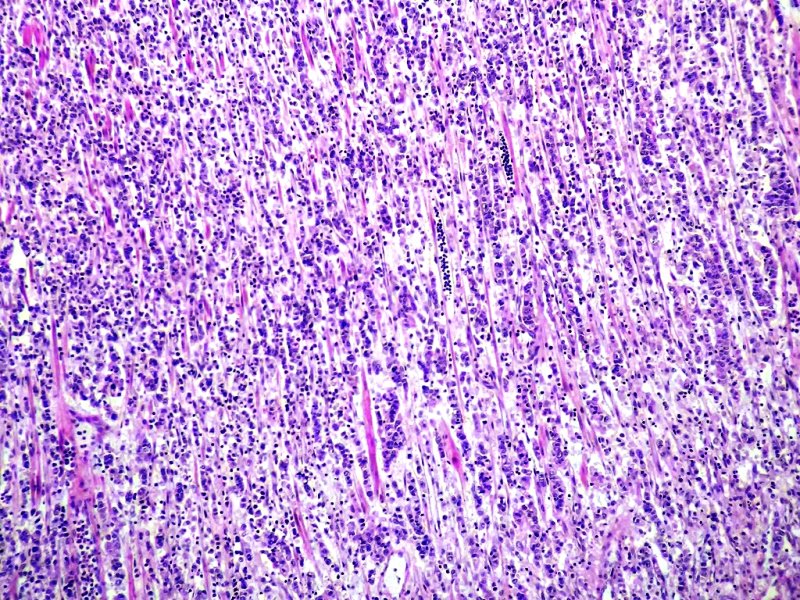

Anapat@Anapat_Lab·

Estómago. Adenocarcinoma gástrico difuso con estroma linfoide. Tinción HE